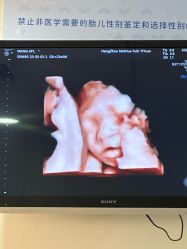

• 杭州贝瑞斯美华妇儿医院·早孕·产检·儿科

• -杭州贝瑞斯美华妇儿医院·早孕·产检·儿科

sammi9219 上传于 23-11-15 | 报错